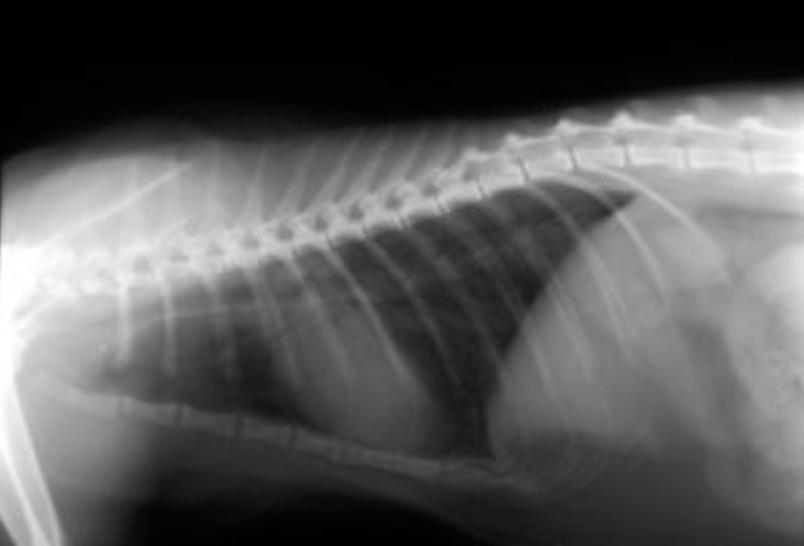

经PCR诊断为继发性支原体感染的哮喘猫的x光片,左侧肺部有斑片状阴影

图片来源:参考文献